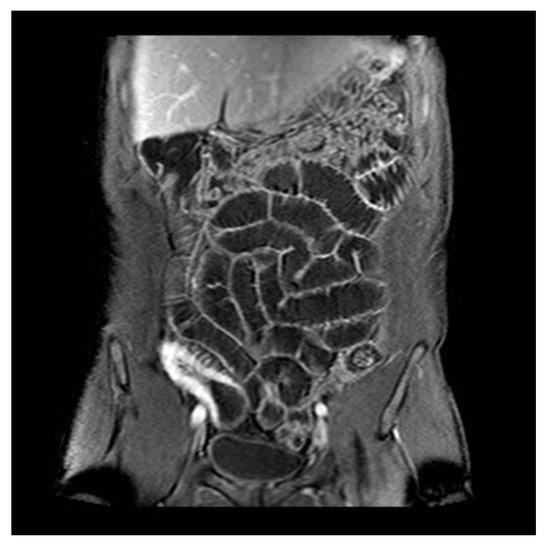

- Punwani, S.; Rodriguez-Justo, M.; Bainbridge, A.; Greenhalgh, R.; De Vita, E.; Bloom, S.; Cohen, R.; Windsor, A.; Obichere, A.; Hansmann, A.; et al. Mural inflammation in Crohn disease: Location-matched histologic validation of MR imaging features. Radiology 2009, 252, 712–720. [Google Scholar] [CrossRef]

- Zappa, M.; Stefanescu, C.; Cazals-Hatem, D.; Bretagnol, F.; Deschamps, L.; Attar, A.; Larroque, B.; Tréton, X.; Panis, Y.; Vilgrain, V.; et al. Which magnetic resonance imaging findings accurately evaluate inflammation in small bowel Crohn’s disease? A retrospective comparison with surgical pathologic analysis. Inflamm. Bowel Dis. 2011, 17, 984–993. [Google Scholar] [CrossRef]

- Bruining, D.H.; Zimmermann, E.M.; Loftus, E.V., Jr.; Sandborn, W.J.; Sauer, C.G.; Strong, S.A. Consensus Recommendations for Evaluation, Interpretation, and Utilization of Computed Tomography and Magnetic Resonance Enterography in Patients With Small Bowel Crohn’s Disease. Gastroenterology 2018, 154, 1172–1194. [Google Scholar] [CrossRef] [PubMed]